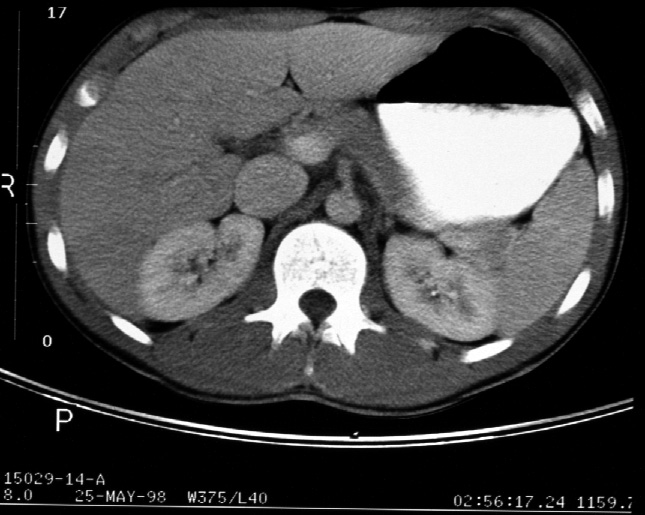

Radiology of Abdomen, Pelvis, and Perineum -- Normal CT Scans of the Upper

Abdomen with Oral and Intravenous Contrast

Identify -- stomach, liver, right kidney, left kidney, aorta, inferior

vena cava, diaphragmatic crura, portal vein, celiac axis, pancreas, spleen